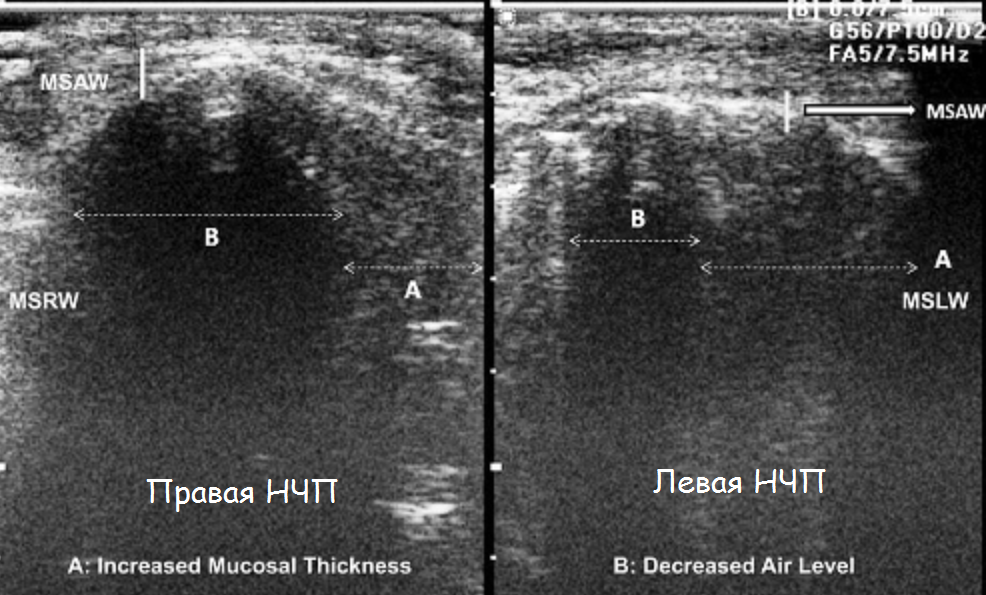

Делают узи носа

Делают узи носа 56 фотографий